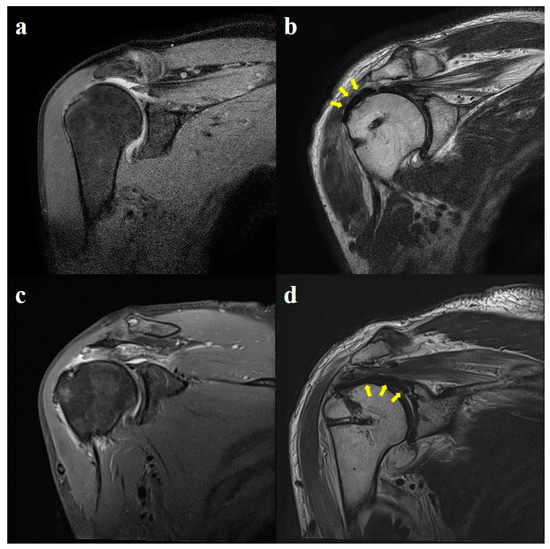

2.4. Radiological Evaluation

3.4. Radiological Outcomes